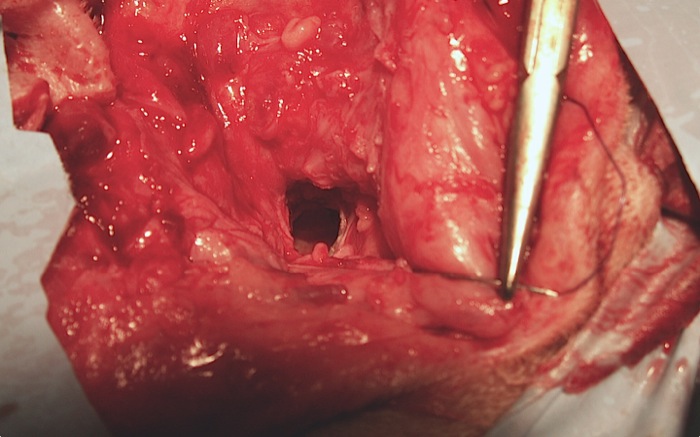

El abordaje es cuidadoso para evitar la lesión del cartílago en todo el conducto hasta el hueso. Comienzo con un corte circular dorsal, disección lateral del canal vertical para ir hacia medial después (foto) y finalmente con la ayuda de separadores de Gelpi ocuparme del canal horizontal.

En ese punto se evita en lo posible el daño neurológico y vascular manteniéndose lo más cerca posible del conducto distal y bulla. En este primer oído operado a pesar de este cuidado se tocó una rama de la arteria carótida externa que produjo un sangrado profuso que se corrigió con presión durante 5 minutos.

Antes de cortar el cartílago, en la unión a la ampolla timpánica, se clampa el conducto con un mosquito para evitar que se vierta contenido de éste al área quirúrgica.